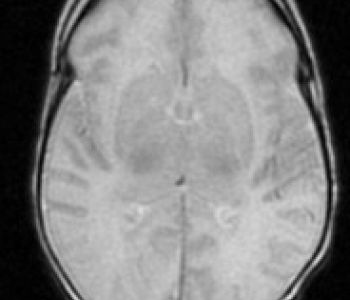

Recién nacido de 35+3 semanas, segundo gemelo de una gestación bicorial-biamniótica que desarrolla en el período fetal un cuadro de crecimiento intrauterino retardado y prenatalmente se detecta una comunicación interventricular, una arteria subclavia derecha aberrante, una arteria umbilical única y una agenesia de ductus venoso.